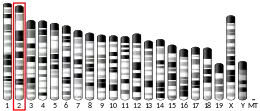

Complement component 5 is a protein that in humans is encoded by the C5 gene.[5]

- Wetsel RA, Lemons RS, Le Beau MM, et al. (1988). "Molecular analysis of human complement component C5: localization of the structural gene to chromosome 9". Biochemistry. 27 (5): 1474–82. doi:10.1021/bi00405a012. PMID 3365401.